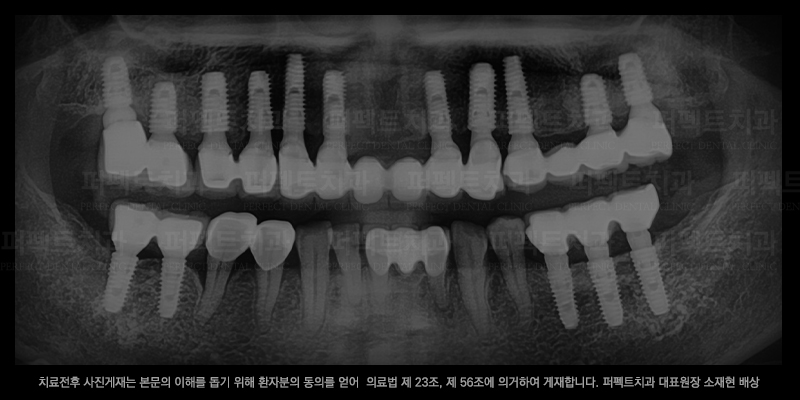

임플란트 전/후 사진 비교

임플란트 수술 후

위 사진은 실제 선릉역치과에서 임플란트 치료를 받으신 환자분의 치료 전/후 사진입니다.

임플란트는 다른 치과치료들 보다 더 신중해야 하는 치료이기 때문에

풍부한 경험과 실력이있는 원장님한테 치료를 받으셔야 합니다.